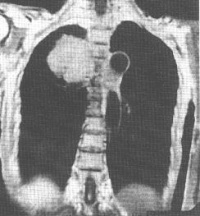

主要为两侧气管旁和肺门淋巴结肿大。通常以气管旁淋巴结肿大为主,并且多为两侧对称性。早期可能仅表现为气管两旁上纵膈阴影轻度增宽。由于此类肿瘤生长迅速,发现病变时,多数明显肿大的淋巴结均已融合成块,使上纵膈向两侧明显增宽,轮廓清楚而呈波浪状,密度均匀。侧位胸片见肿瘤位于中纵膈上中部,即气管及肺门区,肿块边界不清楚。钱纵膈胸骨后淋巴结也常被侵及,表现为紧贴于胸骨后的圆形或椭圆形带有波浪状向后突出的阴影。

CT扫描对显示纵膈各组淋巴结肿大有特殊的优点,显著优于常规X线检查。在早期病变,纵膈轻度增宽时,CT扫描可显示肿块的部位和形态符合纵膈的肿大淋巴结,以及各组淋巴结受侵的范围,对诊断很有帮助。

何杰金病侵犯纵膈交非何杰金病更为多见,而且较易表现两侧病变大小不对称。孤立的前纵膈病变,

不伴有气管旁和肺门淋巴结异常,但常伴有颈部淋巴结肿大。这类类型的淋巴瘤在X线表现上甚似胸腺瘤,在病理上常可见在肿瘤内有残留的凶险组织。

纵膈的淋巴瘤也可侵犯膈神经、喉返神经、交感神经,出现相应的神经麻痹症状,但一般不如转移性淋巴结易发和显著。侵犯心包产生心包积液。瘤住址可经肺门沿支气管周围的间质向肺门侵润,形成自肺门向肺野呈放射状的侵润性条状影及细小结节影。常侵及胸膜产生胸腔积液。胸腔积液也可因纵膈的淋巴瘤阻塞了淋巴液的引流造成。此型胸腔积液,在纵膈淋巴瘤经放射治疗好转后可自行吸收。